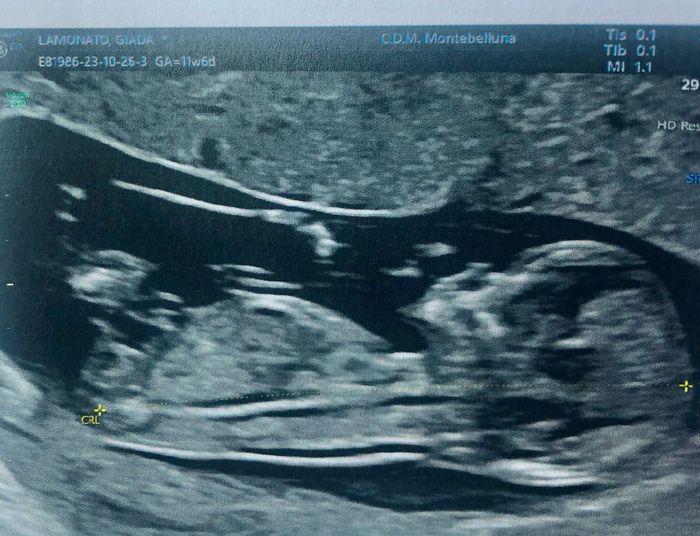

Ciao ragazze! Nell'attesa chi vuole giocare con me? Secondo voi è maschio o femmina? Fatta eco stamattina a 11+6! Io onestamente non saprei dire☺ ho letto la teoria Nub theory ma non riesco a interpretare la mia eco!